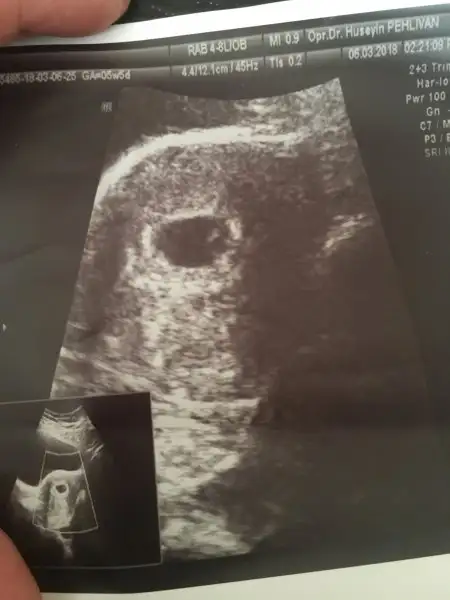

Canım bana da yorum yapar mısın? Karından bakıldı

Eklentiler

• 8CD71E3E-CABC-475C-9CD8-7960D63E37F6.webp

12,7 KB · Görüntüleme: 66

• IMG_20180308_163156.webp

18,2 KB · Görüntüleme: 59